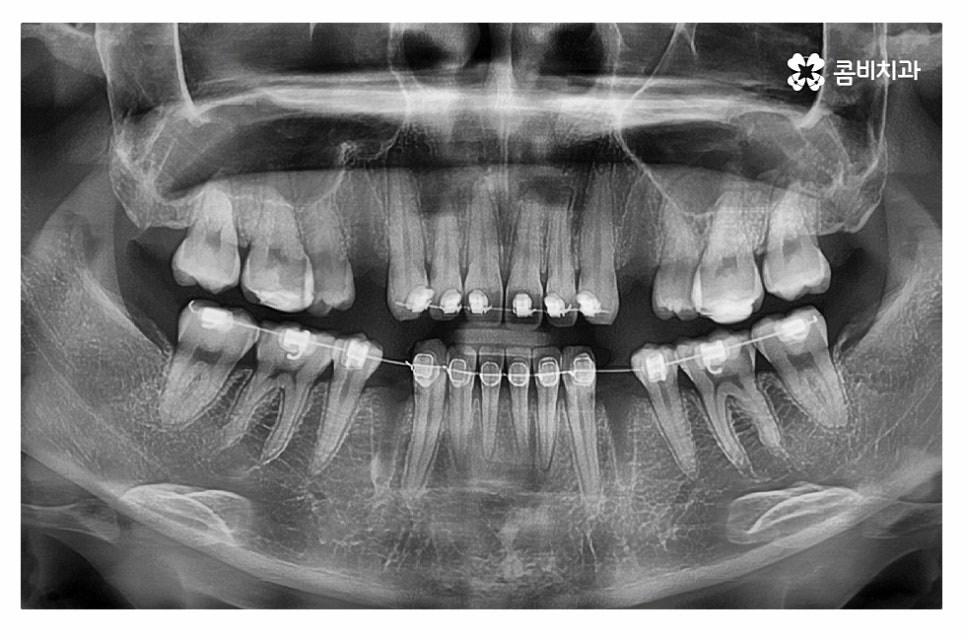

위 환자분의 경우 정면에서 보이는 치열은 가지런한 편이지만

치아가 돌출되어 돌출입으로 고민했던 사례이며

치아의 이동 공간 확보를 위해 발치 교정을 진행한 사례라고 할 수 있어요.

돌출입치아교정은 돌출입의 원인을 정확하게 파악하는 것이 중요한데

일반적으로는 발치를 하는 경우가 많지만 구강구조 및 골격 등은

개인에 따라 다르기 때문에 치간 삭제, 구개확장 장치 등을 활용하여

비발치로도 치아의 이동 공간을 확보하여 비발치치아교정을 하는 사례도 있어요.